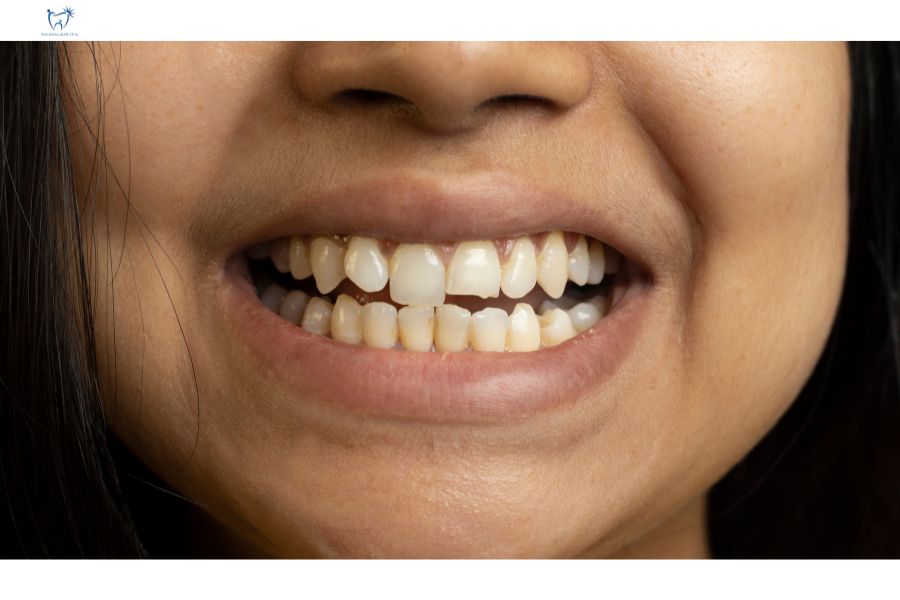

Cầu răng sứ bị mẻ ở răng cửa

Cầu răng sứ bị mẻ là tình trạng phổ biến sau 5-10 năm sử dụng, xuất phát từ chất lượng sứ kém, kỹ thuật thực hiện không chuẩn hoặc thói quen ăn uống không đúng cách. Giải pháp khắc phục bao gồm mài đánh bóng với mẻ nhỏ hoặc thay cầu sứ mới cho răng mẻ lớn.